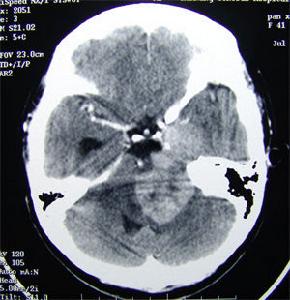

3.CT及MRI檢查 起源於小腦幕切跡處的腦膜瘤沿小腦幕緣向鄰近生長由於跨小腦幕處生長受阻,常形成一切跡近岩骨部位的腦膜瘤可類似腦橋小腦角處腦膜瘤。來自橫竇或竇匯區的腦膜瘤向幕上或幕下生長,軸位掃描很難判斷腫瘤與小腦幕的關係應行冠狀位掃描而橫竇、竇匯區的腦膜瘤常引起局部骨質增生甚至引起橫竇竇匯內血栓形成MRI可清楚顯示腫瘤與鄰近血管、血竇及腦幹的關係由於血管的“流空效應”在T1和T2加權像上均為低信號,與周圍腫瘤組織形成明顯對比MRI亦可顯示腦膜瘤引起的顱骨改變,但不及CT清楚。